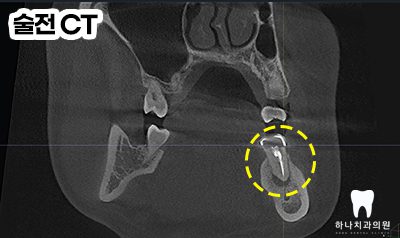

우선 CT 촬영 후 사진에서 보았을 때

원심 근관의 충전을 보면 중앙을

충전물이 지나지 않는 것을

확인할 수 있었습니다.

모든 근관은 치근의 중앙을 지난다는

원칙에 위배되어 하나의 근관이

더 있다는 결론을 도출할 수 있었는데요.

이미 충전된 3개의 근관 충전물을

모두 제거하고 처음 치료 당시

찾지 못했던 숨은 근관도 1시간

넘는 시간을 들여 찾아내었습니다.